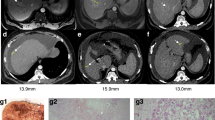

One pig (R1) developed mild hepatic fibrosis (Fig. 4), and another pig (R4) showed mild lobular inflammation after SBRT. Histological features in liver tissue sections from the remaining irradiated and control pigs were normal with regard to fibrosis, steatosis and lobular inflammation. However, when compared with controls, immunohistochemically stained sections from irradiated pigs contained a significantly higher number of hepatocytes undergoing both mitosis (PH-H3; median 17.0 positive hepatocytes per 10 HPFs vs. 3.6 positive hepatocytes per 10 HPFs; P = 0.016) and proliferation (Ki-67; median 76.3 positive hepatocytes per 10 HPFs vs. 12.8 positive hepatocytes per 10 HPFs; P = 0.016) (Fig. 5). There was no difference in the number of hepatocytes undergoing apoptosis in the two groups (caspase-3; median 13.8 positive hepatocytes per 10 HPFs vs. 14.9 positive hepatocytes per 10 HPFs; P > 0.3). In addition, we found a highly significant correlation between proliferative activity estimated from Ki-67 staining and AST levels in blood on the day of liver PET studies (R2 = 0.970, P < 0.0001) for all pigs.

Histological images from a control pig (Pig C4; a,c) and an irradiated pig with hepatic fibrosis (Pig R1; b,d). (a,b) Tissue samples sections stained with Masson’s trichrome stain for evaluation of hepatic fibrosis in a control pig (a) and an irradiated pig (b) with mild fibrosis. (c,d) Tissue sections immunohistochemically stained with an antibody against the nuclear antigen Ki-67, specific for hepatocytes in the proliferating phases of the cell cycle. When compared with the control pig, the number of proliferating hepatocytes in the irradiated pig (d) is markedly higher.